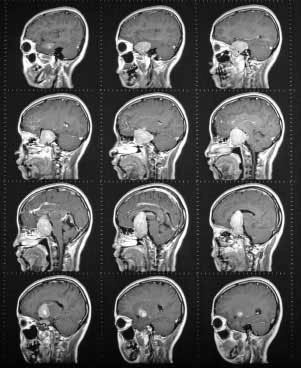

МРТ гипофиза с контрастом

При диагностике нарушений гормонального фона нередко возникает необходимость сделать МРТ гипофиза с контрастом. Это исследование позволяет выявить многие виды патологий мягких тканей – опухоли, воспалительные процессы, ухудшение кровоснабжения и др.

Исследование, основанное на резонансных колебаниях атомов водорода в магнитном поле, позволяет получить достаточно отчетливые изображения сканируемой области. Введение контрастного вещества усиливает возможности томографа и помогает обнаружить опухоль в начальной стадии развития.

Изображения, полученные при помощи томографа, позволяют убедиться в наличии либо отсутствии аденомы гипофиза, которая наиболее часто становится причиной нарушений функции железы. Кроме того, исследование позволяет обнаружить другие патологии тканей – воспаления, травмы и др.